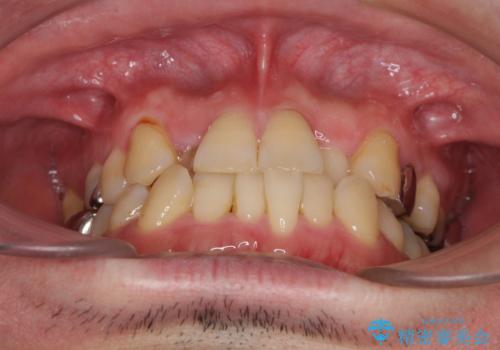

左右下顎の大臼歯は、ともに歯根が破折しており、抜歯が必要な状態でした。

放置したことで炎症による骨吸収が顕著であるため、骨造成を併用してインプラント埋入を行うこととしました。

咬み合わせは受け口傾向であり、上顎前歯の叢生が顕著であったことから、第1小臼歯抜歯による矯正治療も検討しましたが、下顎大臼歯を左右ともに抜歯するため、非抜歯による矯正治療を行うこととしました。